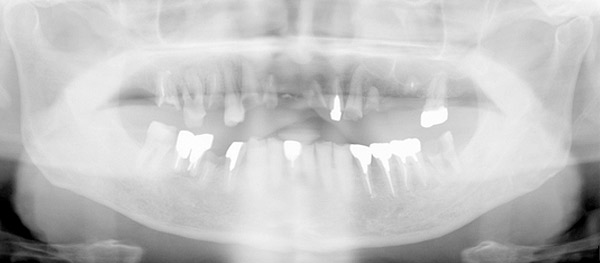

67歳男性の方です。初診時は、本人も上顎の歯すべて抜歯になり、総入れ歯を覚悟していたそうです。できる限り天然歯を温存し、治療は1年8ヶ月という長い期間かかりましたが、包括的な総合的治療により患者様に大変喜んで頂けるゴールを迎える事が出来、先日メンテナンスへ移行しました。

初診時